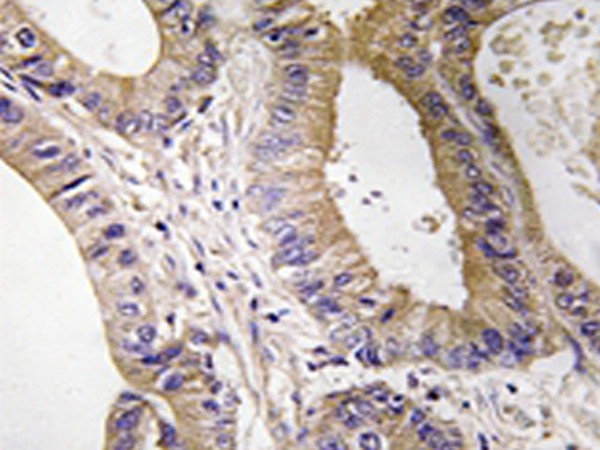

IHC positive control: |

Human colon carcinoma tissue |